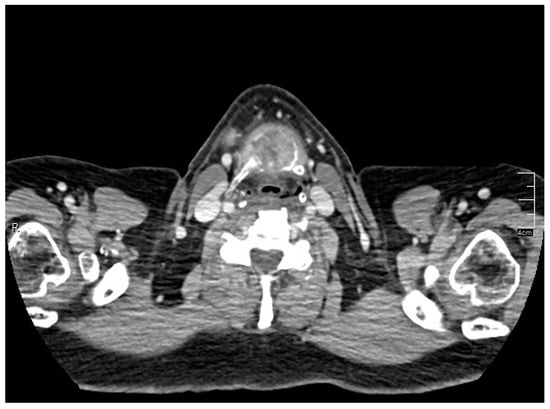

A rounded osteolytic mass of 4.5 × 3.6 cm in size in the central part of the hyoid bone was evident from a contrast-enhanced computed tomography (CT).

CT demonstrated massive osteolysis and cortical destruction with the enlargement of the body of the hyoid bone. The osteolytic mass of the hyoid bone showed a slight soft tissue extension toward the pre-epiglottic region. An evident extension towards pre-hyoid muscles was also noted. The lumen of the airways was not affected, and no pathological changes were evident in the surrounding structures of the neck (Figure 1, Figure 2 and Figure 3).

Figure 1. Contrast-enhanced computed tomography (CT) showed a rounded osteolytic mass of 4.5 × 3.6 cm in size in the central part of the hyoid bone: coronal view.